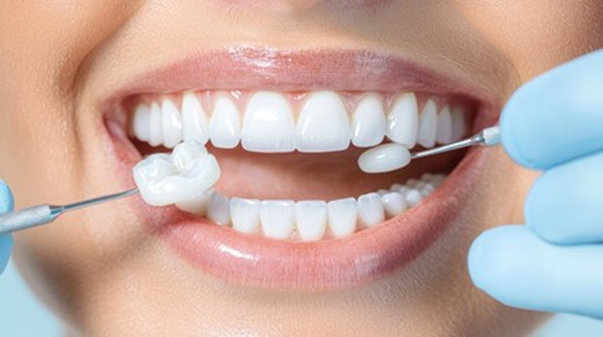

自然な色調を再現できる素材を選ぶことで、見た目を改善することが可能です。そのため、銀歯や変色した歯をセラミックに替える方が増えています。

◼️セラミック治療とは

セラミック治療は、見た目の美しさだけでなく、金属を使わない安心感も魅力の一つです。まずは、その仕組みと特徴を理解しましょう。

セラミックは、陶器に似た素材を歯科用に強化したもので、自然な透明感を持ち、金属を使わないためアレルギーの心配が少ない点が特徴です。

虫歯治療後の被せ物(クラウン)や前歯の形を整える際に使用されます。